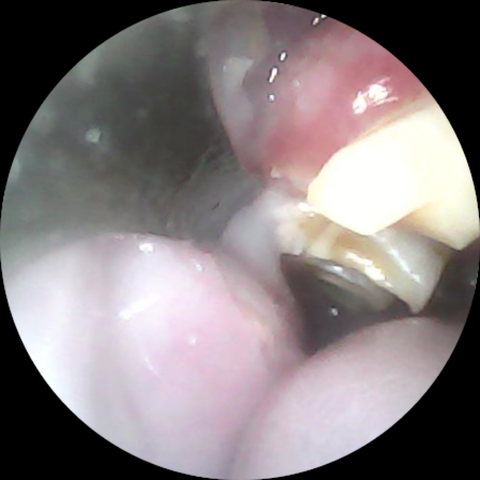

臼歯は、噛み合わせが悪いせいで摩耗せずに過長すると、舌や頬粘膜に刺さってかなりエグることがあります

(右下顎臼歯が舌に刺さって傷つけていた、カット後の様子)

(頬粘膜側に伸びていた右上顎臼歯の棘をカットしたビフォーアフター)